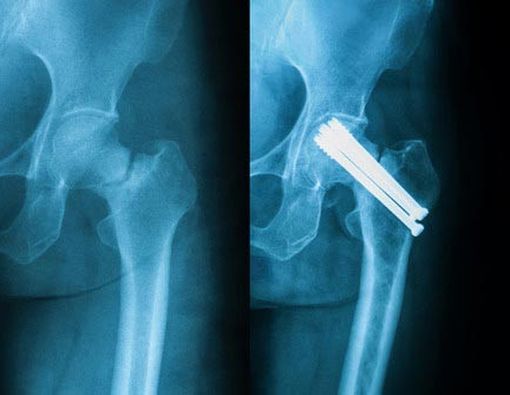

Untuk menentukan penanganan patah tulang pinggul harus dilakukan pemeriksaan fisik lebih lanjut dan pemeriksaan penunjang seperti sinar-X untuk mengetahui tingkat keparahan dari fraktur pinggul yang dialami. Setelah positif didiagnosis mengalami patah tulang pinggul, langkah penanganan yang akan dianjurkan selanjutnya meliputi:

- Prosedur operasi seperti memasang pen atau sekrup, mengganti sebagian tulang paha atau mengganti seluruh sendi panggul.